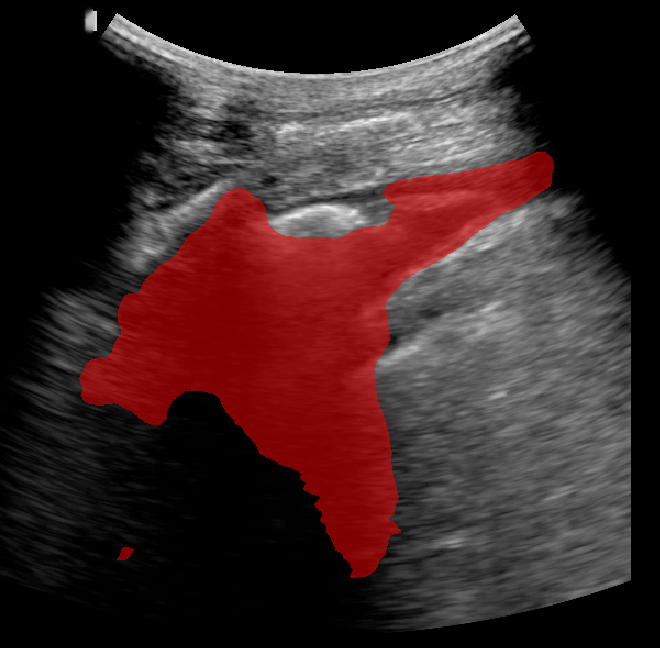

A total of 143 images were acquired from 59 patients. The images were obtained at the left and right PLAPS (PosteroLateral Alveolar and/or Pleural Syndrome) and subcostal views [4] with linear array and curved array (abdominal) ultrasound probes. The data were split according to the use of these probes into two datasets of 51 and 92 images, respectively for linear array and curved array. We denote these datasets as Dataset A (linear array) and Dataset B (curved array). All images were annotated at the time of acquisition to measure the extent of the effusion. These annotations consisted of small crosses at the top and bottom of the deepest area of effusion. See Figure 1 (left column) for example images.

Before being used for training and evaluating the models, each image was automatically cropped using a rectangular/cone mask to remove non-imaging content. Next, we applied an inpainting text algorithm using keras-ocr followed by template matching and edge detection algorithms from opencv to remove the annotations that were added to the images to measure the effusion. Examples of the outputs of this preprocessing are shown in Figure 1 (centre column).

All images in both datasets were manually segmented using the ITK-SNAP software [14] (www.itksnap.org) by a trained observer. Examples of ground truth segmentations are shown in Figure 1 (right column). These segmentations acted as ground truths for training and evaluating the proposed models. Additionally, a second trained observer performed independent segmentations of subsets of 10 random images each from the two datasets. These were used to compute an estimate of inter-observer variability in the manual segmentation process.

Qualitative prediction results of the two proposed models (baseline nnU-Net and nnU-Net with coordinate convolutions) on the two datasets are shown in Figure 2. Tables 1 and 2 summarise the quantitative performances in terms of DSC and area statistics. Histograms of the DSC values are shown in Figure 3. The median DSCs between the manual segmentations on the subsets of 10 images (i.e. the estimates of inter-observer variability) are also shown in Table 1.

Rows 1-2: Dataset A. Rows 3-4: Dataset B.